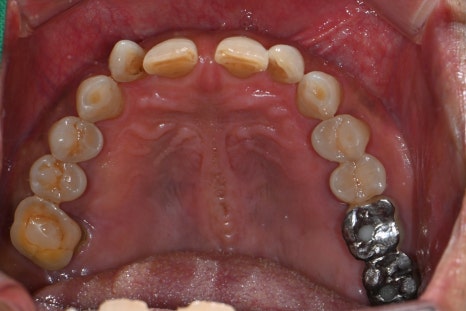

왼쪽 사진: 최종 보철 장착 후 촬영한 파노라마 엑스레이입니다.

오른쪽 사진 : 치료가 마무리된 후의 구강 내 사진입니다.

보철물은 지르코니아 재료로 제작되어 단단하면서도 심미적이며, 자연치와의 조화가 뛰어나게 마무리되었습니다.